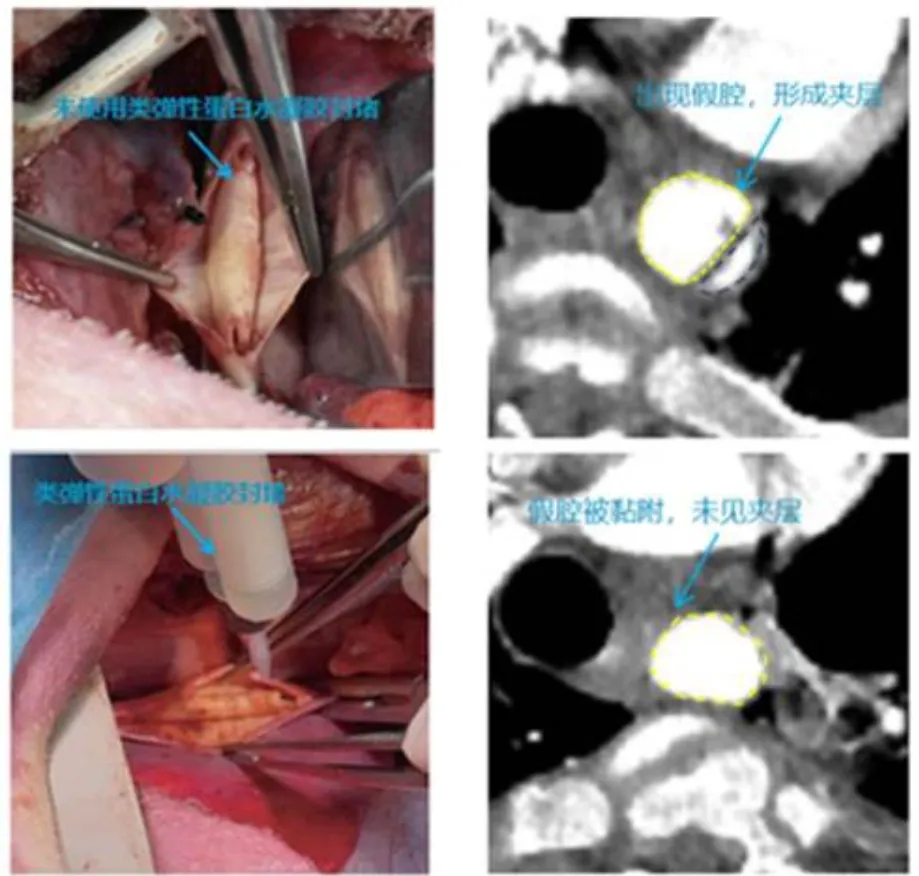

(1)主动脉夹层(大型动物猪)

模型:手术制备主动脉假腔(长度4 cm)

处理:注射1 mL水凝胶至假腔,缝合外膜

结果:术后CTA证实假腔完全闭合,夹层治愈